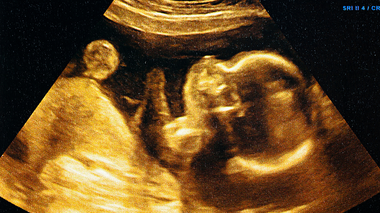

3. Can a sonography detect changes in a baby’s skin?

A sonogram cannot directly show how thick the baby’s skin is. It’s useful for evaluating fat deposits and how well the baby is growing.